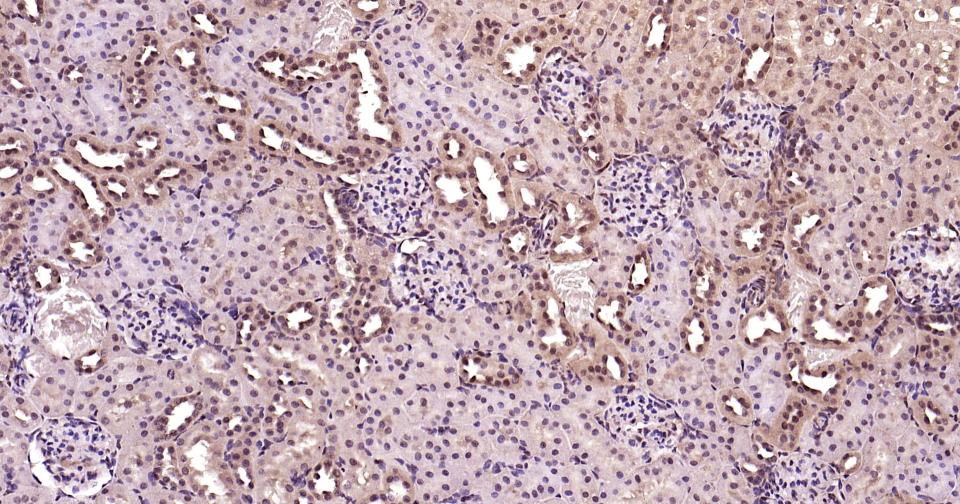

Paraformaldehyde-fixed, paraffin embedded Rat Kidney; Antigen retrieval by boiling in sodium citrate buffer (pH6.0) for 15 min; Antibody incubation with K48-linkage specific ubiquitin? Monoclonal Antibody, Unconjugated(bsm-63005R) at 1:200 overnight at 4°C, followed by conjugation to the bs-0295G-HRP and DAB (C-0010) staining and DAB (C-0010) staining.

Paraformaldehyde-fixed, paraffin embedded Mouse Kidney; Antigen retrieval by boiling in sodium citrate buffer (pH6.0) for 15 min; Antibody incubation with K48-linkage specific ubiquitin? Monoclonal Antibody, Unconjugated(bsm-63005R) at 1:200 overnight at 4°C, followed by conjugation to the bs-0295G-HRP and DAB (C-0010) staining and DAB (C-0010) staining.